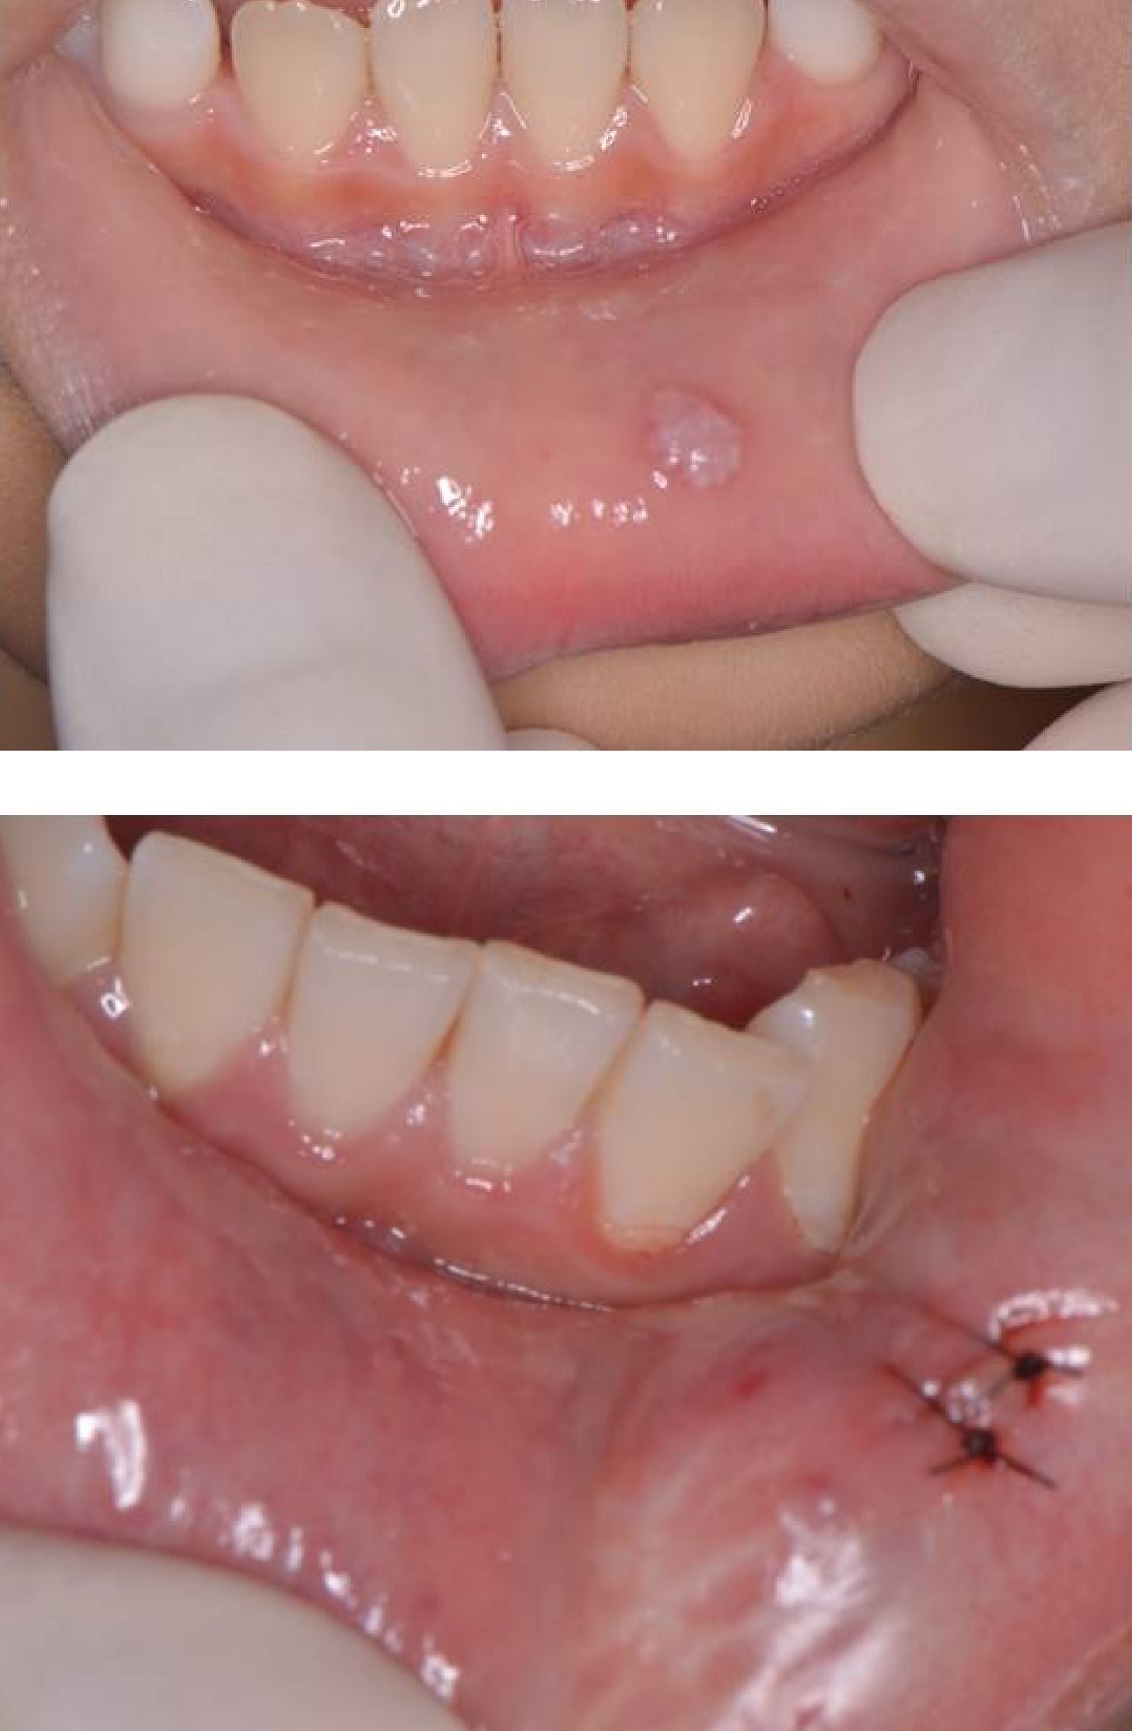

Explore effective oral mucocele treatments to manage and remove these fluid-filled cysts. Learn about professional medical procedures, including surgical excision, laser ablation, and cryotherapy, to ensure safe recovery. Understand the underlying causes, symptoms, and when to consult a dentist for expert diagnosis and long-term relief from recurring mucous cysts inside your mouth.

TitleMucocele excision - surgical removal of a soft tissue lesion | Ho Dental Office | Dentist ...